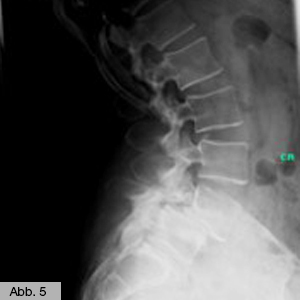

Einen weiteren Schwerpunkt unserer Orthopädie bildet die Behandlung der Instabilität der Wirbelsäule, wie z.B. eines Wirbelgleitens (Spondylolisthese), wobei sich der obere Wirbelsäulenanteil meist gegenüber dem darunterliegenden Wirbelsäulenanteil nach vorn verschiebt. Von diesem Krankheitsbild sind häufig ältere Menschen betroffen. Die konservative Therapie erstreckt sich dabei von der Stützung des Rumpfes mittels einer Rumpforthese über Physiotherapie bis hin zu einer Schmerzbehandlung mittels Infiltrationstherapie (Gabe von Flüssigmedikamenten in die Haut oder tiefer liegende Bereiche) oder PRT (Periradikuläre Therapie, Gabe von Medikamenten direkt an die Nervenwurzel). Bei mangelndem Erfolg der konservativen Maßnahmen entscheiden unsere Fachärzte je nach Symptomatik und Einzelfall, ob eine Operation eine Linderung der Schmerzen bewirken kann – im Falle chronischer Nervenschädigungen oder ausgeprägter statischer Haltungsschäden muss das betroffene Wirbelsegment in einem operativen Eingriff (Spondylodese) reponiert und anschließend versteift werden (Abb. 5 & 6).

Bild Orthopädie Spondylodese

Bild Orthopädie Spondylodese OP